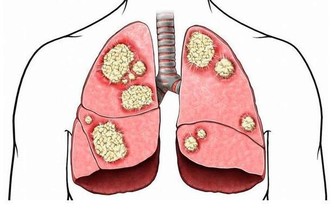

但是醫學研究發現痛風產生的尿酸結石等病變早期主要影響腎小管的重吸收功能,使人體濃縮尿液的能力下降,這是在悄無聲息損傷痛風患者的腎臟,而且並不一定會反應為血肌酐升高。所以,在腎內科一般都認為痛風都會百分百引發腎臟損害!

如果不幸遇上了痛風,建議你別學傻狍子埋雪地,疼的時候才想起來這個事兒,緩一緩後又忘記了,要做的是在一個週期內盡可能減少疼的次數,同時也就是減少了腎臟損害的次數。